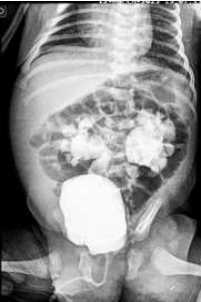

Orgão: SES-PE

Lactente masculino de 14 meses está internado em enfermaria de pediatria para tratamento de uma pielonefrite aguda, por meio de antibiótico venoso. Solicitada ultrassonografia renal e de vias urinárias que evidenciou, apenas, hidronefrose bilateral. A mãe do menor relata outros dois internamentos prévios pelo mesmo diagnóstico (o que foi comprovado pelos resumos de alta). Paciente recebeu alta com quimioprofilaxia oral e solicitação para realizar uretrocistografia miccional (UCM) em nível ambulatorial, desde que urocultura negativa. A UCM foi realizada, e uma das imagens encontra-se abaixo:

II. A imagem da UCM evidencia achados típicos de válvula de uretra posterior.

III. A cintilografia renal com ácido dimercaptosuccínico-tecnécio-99 deve ser solicitada, pois a principal hipótese diagnóstica para este lactente é de estenose da junção ureteropélvica à direita e displasia renal à esquerda.

IV. A hipótese mais provável para este paciente é de estenose da junção ureterovesical à direita e megaureter à esquerda.